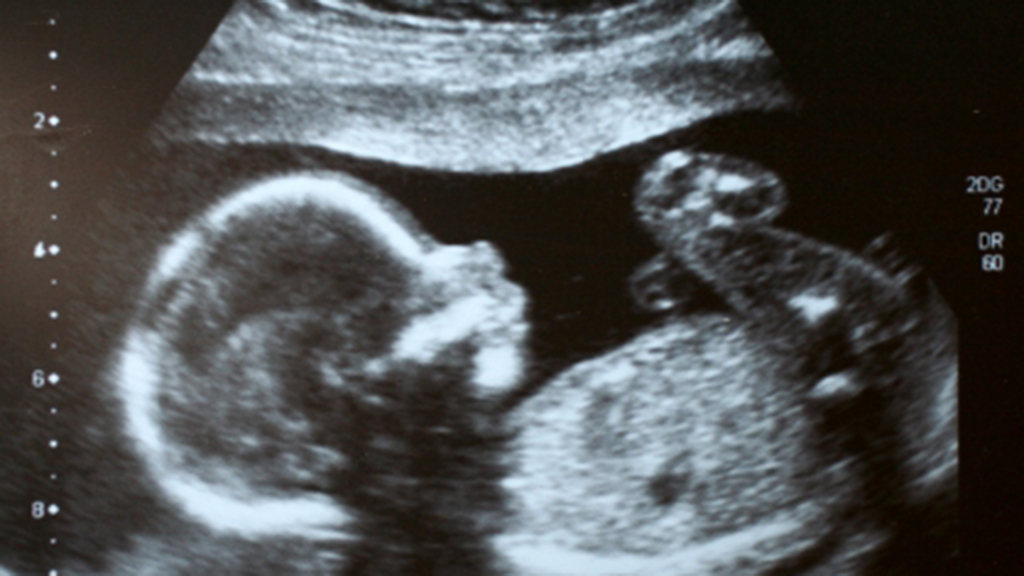

This case study follows a woman faced with a series of difficult medical decisions. Students apply systems-level physiology as they explore a pregnancy with medical complications and discuss situations involving life-changing decisions prompted by modern medical technologies. This case could be used in an advanced biology course at the high school level, or in undergraduate courses in general biology, human anatomy and physiology, human health, human sexuality, medical ethics, sociology, or women’s studies. The case study also would be applicable to first-year medical students in a course in medical physiology as well as students in nurse practitioner, midwifery, or physician’s assistant programs.